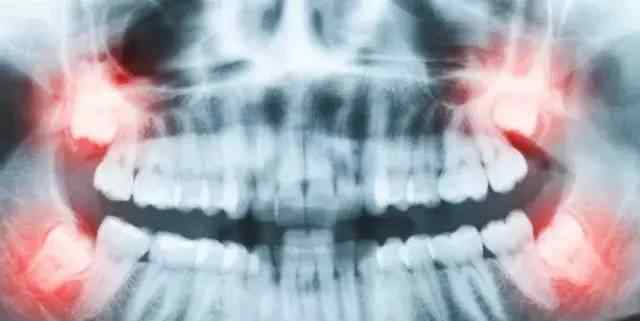

但是也有智齿长出来却不萌的情况,所以这个时候需要拍照才能看到。特别注意下图中的阻生智齿很容易使门牙倾斜,或者使门牙倾斜,危害极大,建议定期拍照查看。

邻牙病变通常没有感觉,大部分是牙医通过X线诊断发现的。这是由于智齿萌出空不足,异位阻生靠在第二磨牙上,使第二磨牙难以清洁,甚至使第二磨牙部分吸收,严重时可能引起不适或疼痛。

阻生智齿

通常这是最麻烦的一个。这颗智齿通常埋在牙槽骨中。如果经常发生炎症,或者诊断出病变,必须切除。